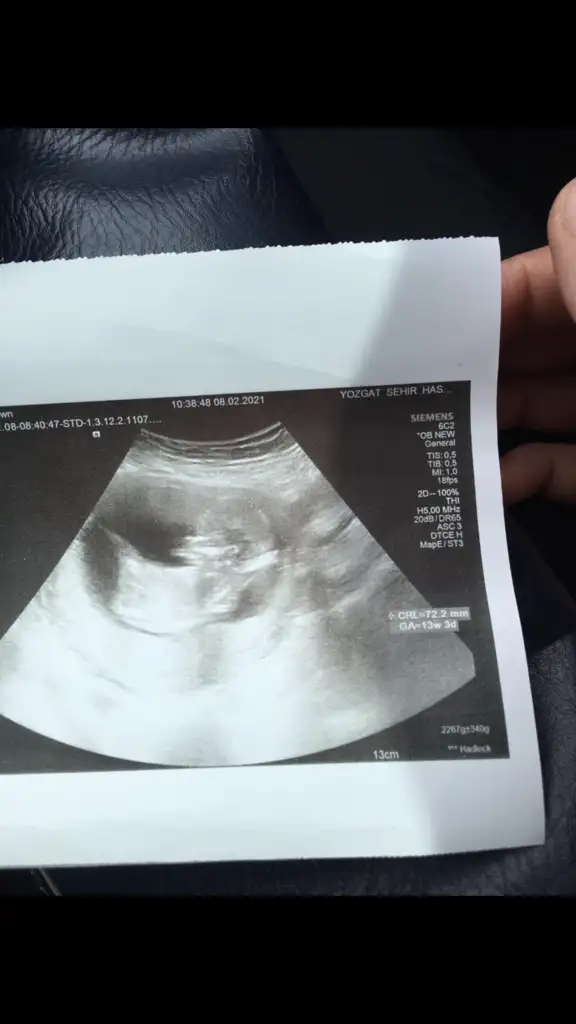

• Screenshot_20210205-150944_Video Player.webp

Screenshot_20210205-150944_Video Player.webp

13,9 KB · Görüntüleme: 71

Merhaba lutfen yardimci olurmusunuz 11 hafta 6 gunluk karindan ultrason